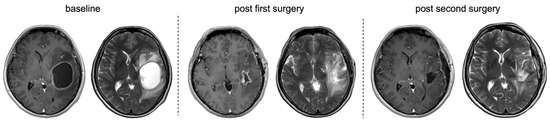

From a Polymorphous Low-Grade Neuroepithelial Tumor to a Glioblastoma in an Adult Patient with FGFR3-TACC3 Fusion: A Case Report and Literature Review of the Molecular Profile

by Lorena Gurrieri, Nada Riva, Alessia Tomassini, Giulia Ghigi, Maurizio Naccarato, Patrizia Cenni, Daniela Bartolini, Chiara Cavatorta, Luigino Tosatto, Monia Dall’Agata and Laura Ridolfi

Curr. Oncol. 2026, 33(3), 165; https://doi.org/10.3390/curroncol33030165 - 13 Mar 2026

From an epidemiological perspective, polymorphous low-grade neuroepithelial tumor (PLNTY) represents a small proportion of brain tumors encountered in epilepsy surgery series. Their rarity and relatively recent recognition likely contribute to underdiagnosis and poor prognosis. In terms of histopathological features, they are similar to [...] Read more.

From an epidemiological perspective, polymorphous low-grade neuroepithelial tumor (PLNTY) represents a small proportion of brain tumors encountered in epilepsy surgery series. Their rarity and relatively recent recognition likely contribute to underdiagnosis and poor prognosis. In terms of histopathological features, they are similar to oligodendrogliomas. Molecular analyses can be used to show the fusion between fibroblast growth factor receptor (FGFR3) and transforming acidic coiled coil (TACC) proteins, which most commonly results in progression towards glioblastoma (GBM). We report a case of a 62-year-old man who underwent left frontal craniotomy to remove a frontal mass. Histologically, the glial lesion consisted of elements associated with oligodendroglia-like features. Immunohistochemistry was positive for glial fibrillary acidic protein (GFAP), oligodendrocyte transcription factor 2 (OLIG2), and α-thalassemia X-linked mental retardation syndrome (ATRX) nuclear expression, but negative for isocitrate dehydrogenase 1 (IDH1) and BRAF-V600E. Next-generation sequencing showed the FGFR-TACC3 fusion, and taken together, these findings supported the final diagnosis of PLNTY. During follow-up, the patient underwent a second neurosurgery, where histological evaluation indicated a GMB. This article presents clinical and radiological data, morphology, immunohistochemistry, molecular features, and treatment to enhance the clinical and pathological understanding of PLNTY with FGFR3-TACC3 fusion for all professionals involved in medical decisions. Full article